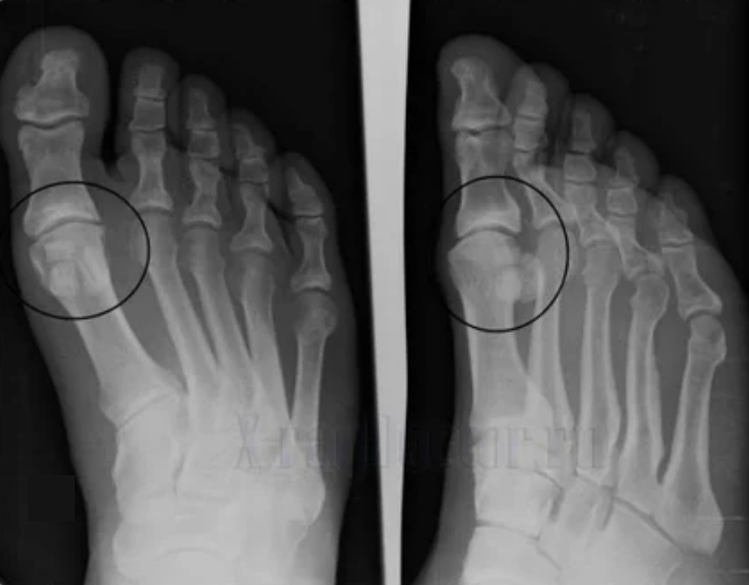

Gliedmaßenverformungen. Es erscheint in einer unachtsamen Art der Krankheit und zeigt die vollständige Zerstörung des Knorpelgewebes und das Erscheinungsbild von Osteophyten an. In diesem Zustand nimmt der Druck auf die Gelenke im oberen und unteren Teil zu, aus dem die Krümmung das gesamte Glied beeinflussen kann.

Es ist wichtig, sich daran zu erinnern, dass die Verformung der Knochen im Bein oft mit Mais verwechselt wird. Das Symptom ist nur auf den ersten Blick nicht sehr gefährlich, führt jedoch zu schwerwiegenden Folgen.

Um eine Diagnose zu stellen, untersuchen Rheumatologen die Beschwerden des Patienten und verschreiben eine X -Ray -Untersuchung. Meistens wird die Radiographie in 2 Projektionen verwendet. Der Arzt analysiert das Vorhandensein von Verteilungsstörungen in den Hyalinenknorpel- und Knochenverbindungen. Wenn die Gelenkspalte verringert wird, die Knochen verzögert oder abgeflacht sind, gibt es zystische Formationen auf der Knorpeloberfläche, Osteophyten sind offensichtliche Anzeichen einer Arthrose. Während der Inspektion zeigt die Arthrose auf die Instabilität der Artikulation an: die Achse der Gliedmaßen und die Subluxation wird verändert.

Oft kann ein X -Ray -Bild keine vollständigen Informationen über den Zustand des Gelenks geben. Für eine gründlichere Studie ist die computergestützte Tomographie verschrieben, und es ist wirksam, die Knochen zu untersuchen. Magnetresonanz wird häufiger zum Untersuchung von Weichgeweben verwendet.